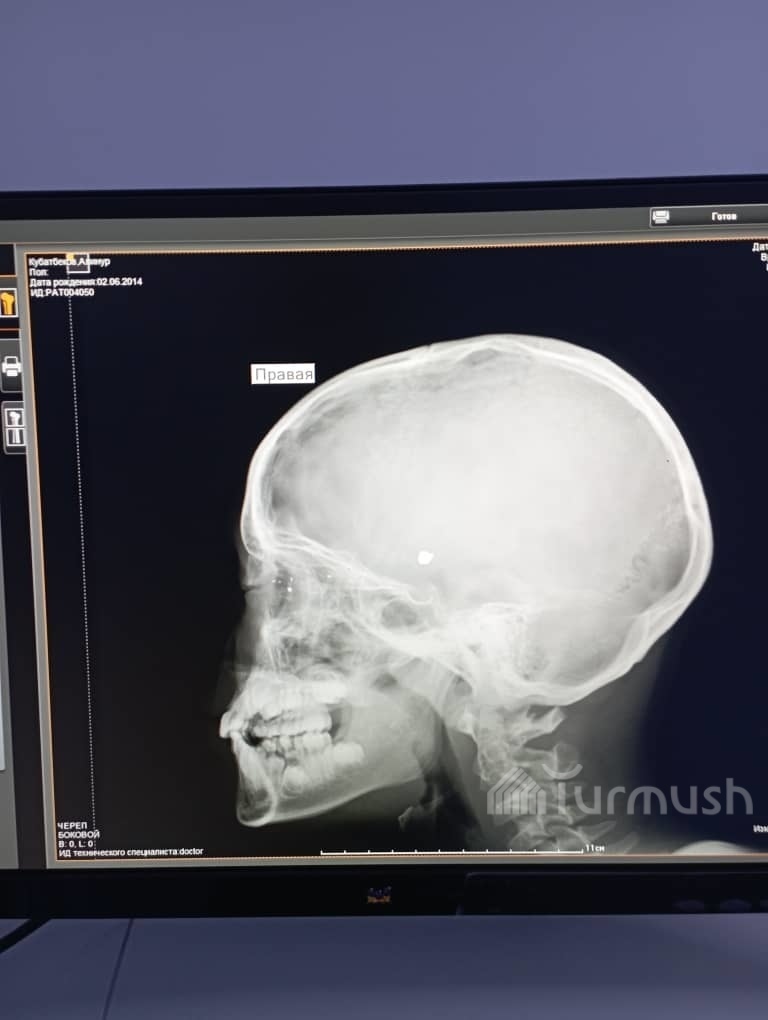

AKIPRESS.COM - Brothers shooting at a shooting range accidentally hit a 9-year-old child in Jerge-Tal municipality of Aksy district, Jalal-Abad region, on Aug 2, Gulbarchyn Rakhmanova, the deputy chief physician of the regional children's hospital, said...